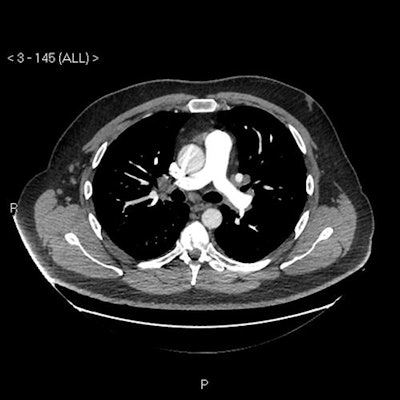

Chest radiograph reported as normal. Note the diffuse ground-glass shadowing in all zones. Images courtesy of Dr. Patrick Liu-Shiu-Cheong, Dr. Owen Dempsey, and BMJ Case Reports 2019."Our patient's CXR [chest x-ray] report was initially reported as normal (although we disagreed)," the authors wrote. "He subsequently had a CT pulmonary angiogram with high-resolution reconstruction (to exclude pulmonary thromboembolic as well as interstitial lung disease), reported as showing a ground glass, mosaic pattern in both lungs, with borderline enlarged hilar nodes, presumed reactive."

CT scan (mediastinal axial slice) with prominent reactive borderline enlarged mediastinal and hilar nodes.Blood avian precipitins were strongly positive, and lung function testing confirmed a restrictive pattern with impaired gas transfer.